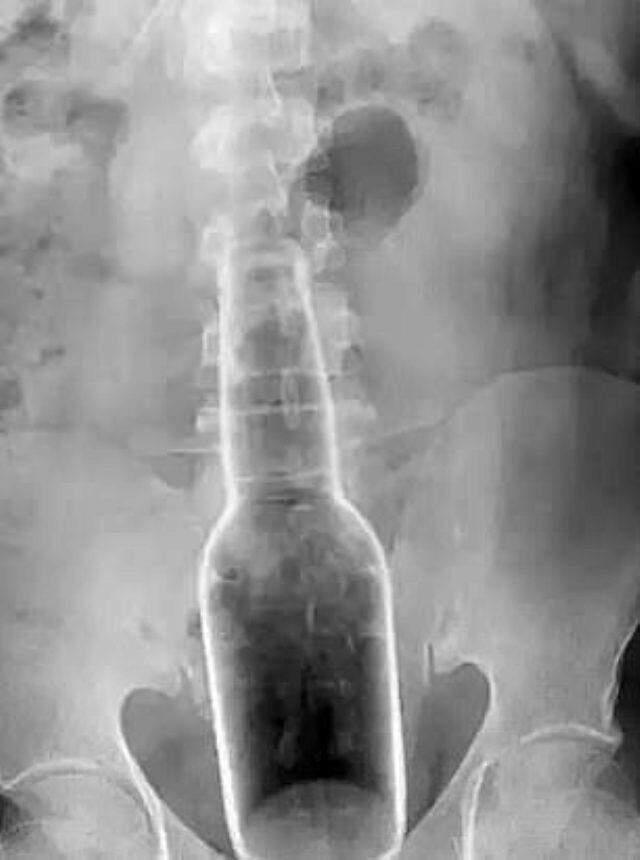

ÇEKİLEN RÖNTGEN, GERÇEĞİ ORTAYA ÇIKARDI

Röntgen tetkiklerinin akabinde, cismin hastanın anüsünden kalın bağırsağına kadar uzanan, 18 santimetre uzunluğunda ve 5 santimetre genişliğinde cam bir şişe olduğunu tespit ettik. Şişeyi çıkarmak hedefiyle hemen operasyon kararı aldık. Operasyon başarılı geçti ve hastamızı tıpkı gün taburcu ettik” sözlerini kullandı.